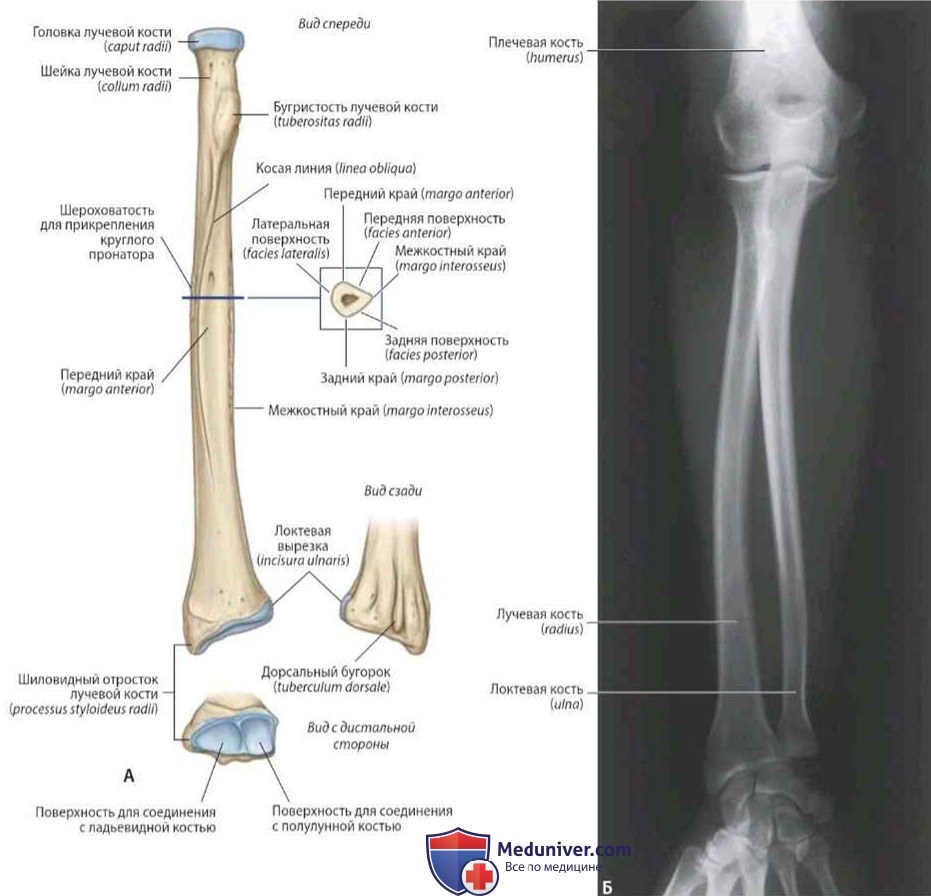

Радиоульнарный угол: строение и особенности лучевой кости